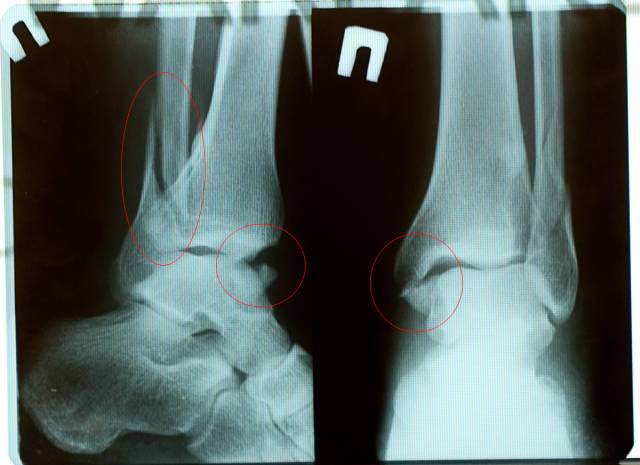

Перелом лодыжек

Перелетел стол, как следствие грохнулся на плошмяк с приличной высоты.

to riget - перелетел стол, с большой высоты пришел на плоскость, после отработки подвески (вилки) спрыгнул с байка назад, правую ногу не успел переместить вперед, сел жопой на пятку, вывех стопы и заодно перелом лодыжек.

Готовься к операции, репозицию латеральной лодыжки консервативным путём будет ой как сложно произвести ;)

Большое спасибо всем за пожелания. На следующей неделе будет консультация с хорошим доктором травматологом, будем думать, что и как оперировать, если конечно это нужно. На данный момент изломы не мешают работе сустава и они срастаются.

Все сраслось, кости сами встали на свои места, оперировать не пришлось. Всем спасибо за пожелания =)